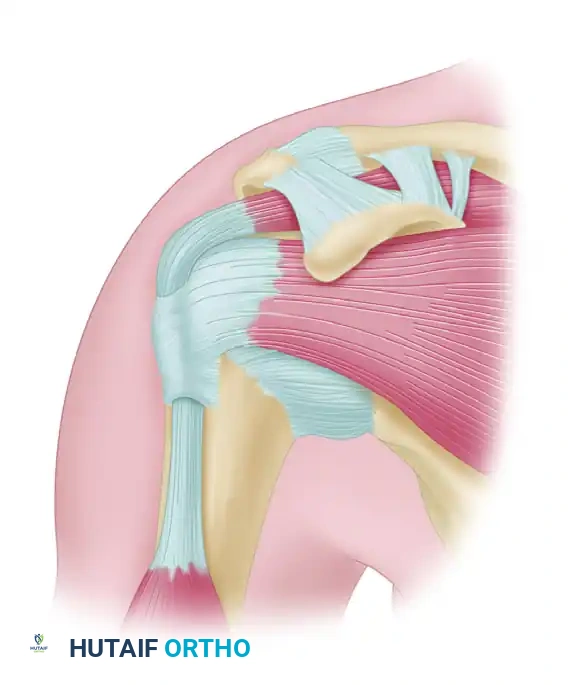

Figure 46-3: Impingement syndrome. The supraspinatus tendon is visualized passing directly beneath the rigid coracoacromial arch, highlighting the anatomical bottleneck susceptible to mechanical compression.

Figure 46-4 (Type I): A flat acromion with minimal compromise of the supraspinatus outlet. Associated with the lowest risk of rotator cuff pathology.

Figure 46-4 (Type II): A curved acromion that parallels the contour of the humeral head, moderately reducing the subacromial space.

Figure 46-4 (Type III): A hooked acromion with a prominent anterior-inferior projection. This morphology severely compromises the supraspinatus outlet.

Cadaveric studies have demonstrated a profound correlation between acromial morphology and rotator cuff integrity. In a landmark study of 140 shoulders, 73% of all full-thickness rotator cuff tears were found in shoulders possessing a Type III (hooked) acromion. Patients with a decreased acromial slope are inherently predisposed to subacromial stenosis and subsequent mechanical attrition of the underlying tendons.